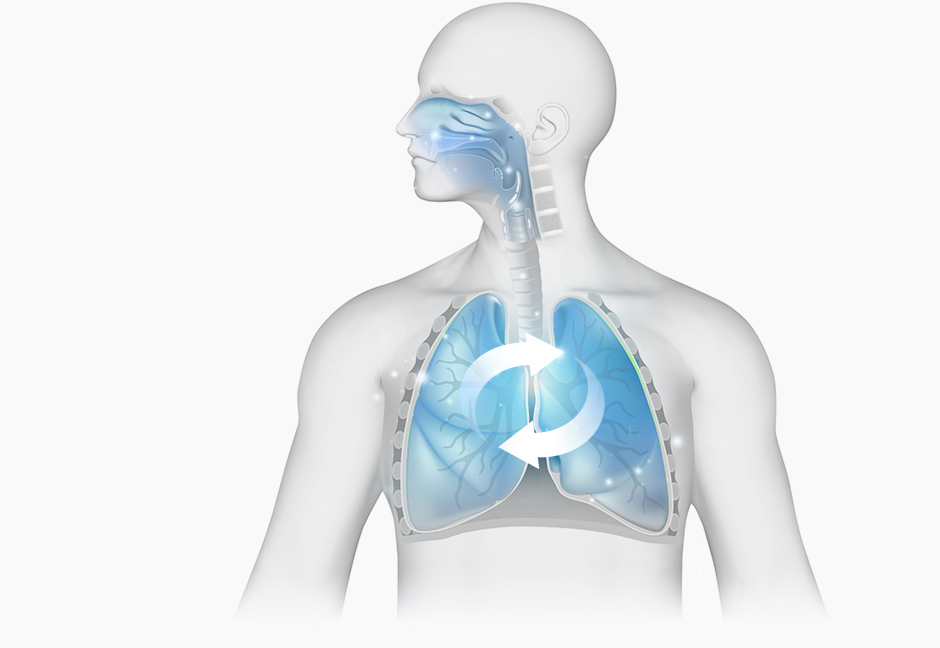

Through the lung-cleansing (Cheongpye) action of Pyunkang-tang, accumulated heat in the lungs is lowered and vitality is replenished. Under the guidance of the lungs—which handle 95% of the body's respiration—the skin, the body's 'minor respiratory organ,' opens its sweat and hair pores to release toxins and waste.

STEP 2

Normalize lung function

with Pyunkang-tang

(Lung function gradually recovers, enabling skin respiration)